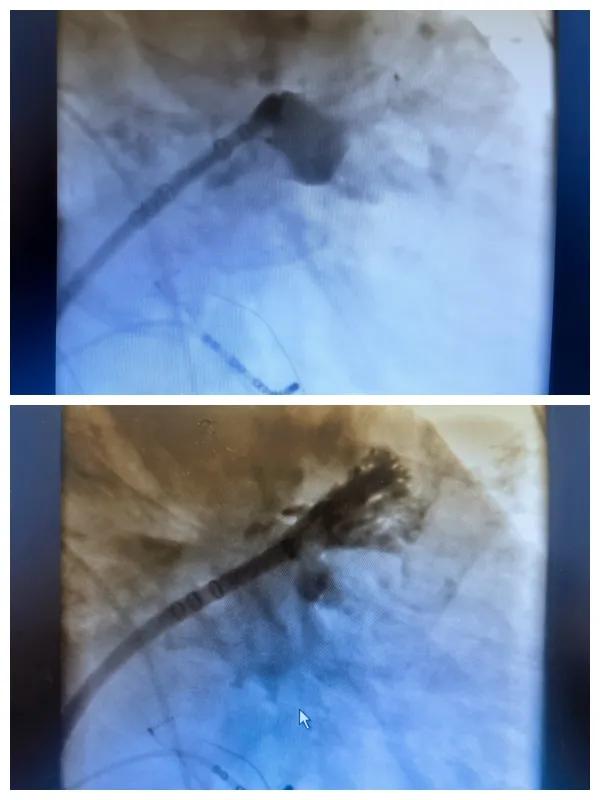

漯河市二院成功開展房顫射頻消融術(shù)+左心耳封堵WM FLX一站式手術(shù),再攀“心”高峰!

房顫射頻消融術(shù)+左心耳封堵WM FLX一站式手術(shù)

6月26日,市二院成功為一名老年房顫患者實(shí)施了房顫射頻消融術(shù)+左心耳封堵WM FLX一站式介入治療,標(biāo)志著醫(yī)院在心律失常介入治療領(lǐng)域邁出了嶄新的一步,開啟了新的治療篇章。

本次手術(shù)特邀我國著名心血管內(nèi)科專家、河南省胸科醫(yī)院黨委書記袁義強(qiáng)及血管內(nèi)科七病區(qū)主任黃瓊教授蒞臨指導(dǎo),市二院院長王瑾帶領(lǐng)心血管內(nèi)科電生理等專家團(tuán)隊(duì)緊密合作,一次性解決了患者房顫、血栓兩大困擾,也使患者告別了終身服用抗凝藥的痛苦,極大地降低了患者的經(jīng)濟(jì)和用藥負(fù)擔(dān)。

為了讓患者得到全面、綜合的治療,經(jīng)過團(tuán)隊(duì)術(shù)前充分討論,并征得家屬同意,心血管內(nèi)科團(tuán)隊(duì)決定采用目前國內(nèi)外先進(jìn)的房顫射頻消融術(shù)+左心耳封堵WM FLX一站式介入微創(chuàng)手術(shù)來治療老人的疾病。整個(gè)手術(shù)過程圓滿順利,術(shù)后何大爺各項(xiàng)體征正常,蘇醒后順利返回病房。